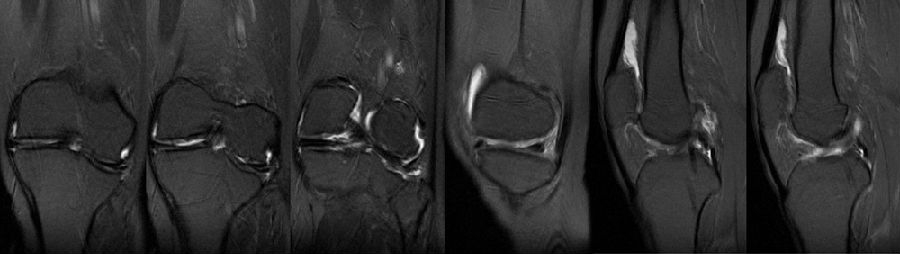

术前MR

该病例特点:患者中年女性,49岁,较活跃;JLCA基本正常,关节线倾斜,下肢力线略外翻;倾斜来源股骨内翻和胫骨外翻;既往股骨远端手术史;陈旧性软组织疤痕,局部畸形,骨质硬化,合页易骨折。

软骨磨损的程度——内外侧局部软骨均有磨损,外侧明显。